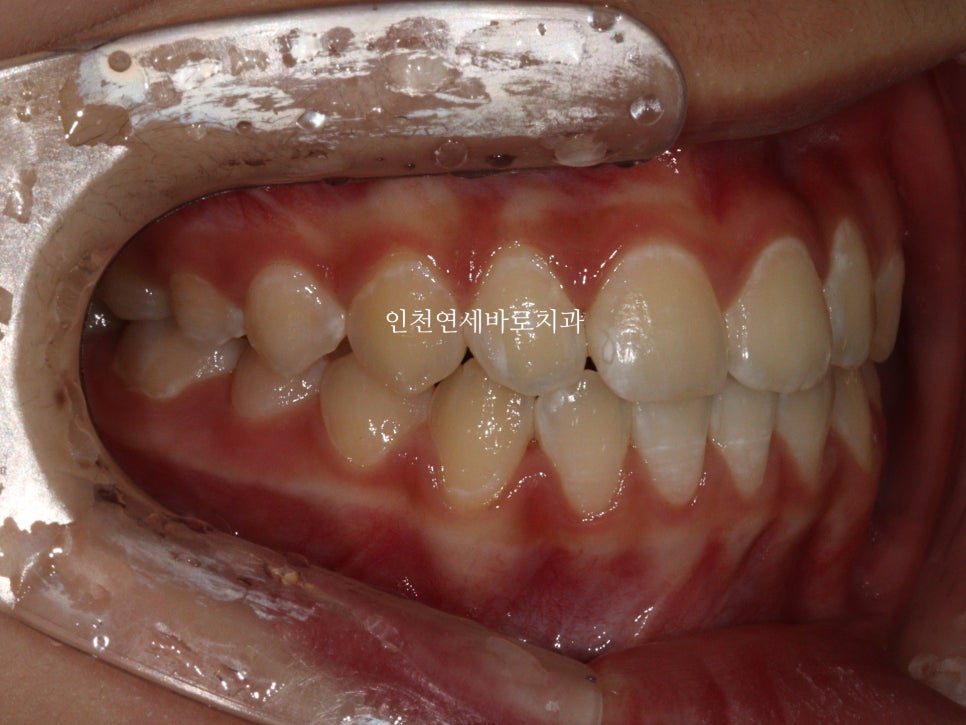

2024년 11월 11일 – 치료 완료

치아배열도 좋습니다.

최후방 치아가 나올때 약간 삐뚤게 나옴으로 인해 1회 재제작을 했습니다.

아이가 치료가 끝난 후 안아프고 좋았다. 친구들이 부러워했다. 라는 말을 해서 뿌듯했습니다.